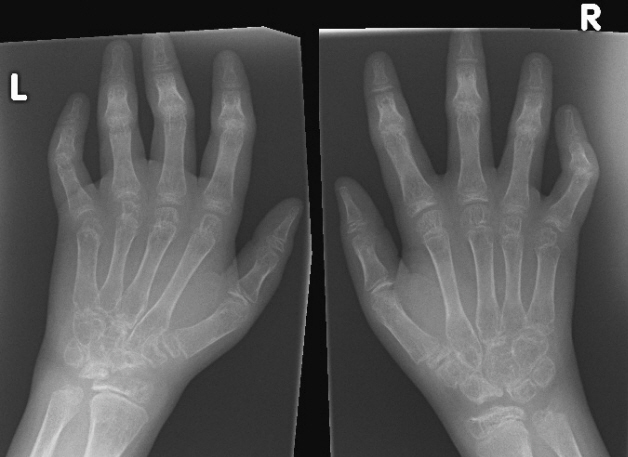

Причем если у взрослых поражение суставов при ревматоидном артрите чаще происходит симметрично, то у подростков могут формироваться единичные очаги болезни.

- При единичных поражениях на фоне здоровых тканей пораженный сустав выглядит намного больше. Его форма становится неровной, кожа на ощупь в месте поражения – горячая, красная. Мягкие ткани сильно отекают и становятся болезненными на ощупь.

Олигоартикулярный ЮИА (юношеский олигоартрит). Отличительный признак этого варианта – поражение до 4 суставов без вовлечения внутренних органов и общих симптомов. Чаще воспаление несимметрично и затрагивает коленные и голеностопные суставы. Олигоартрит часто начинается у малышей до 6 лет, преимущественно у девочек.